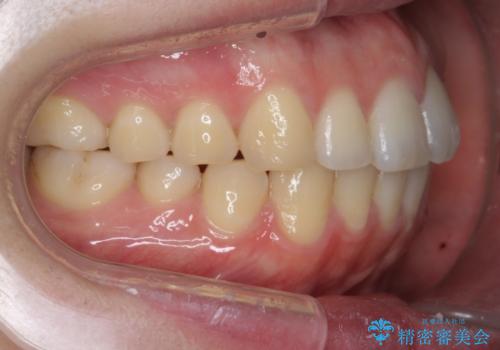

前歯が気になる。インビザラインライト

- 前歯が気になるとの事で来院。

矯正を希望されたが費用と時間を抑えたいとの事でインビザラインライトで矯正を行いました。(奥歯の位置関係はほぼ変えない)

前歯が綺麗に並び大変満足して頂けました。